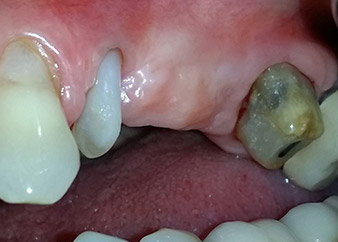

total loss of bone and attachment

Fig. 2 and 3: After raising flaps, one month after endodontic revision and initiation of full-mouth periodontal therapy, the buccal root of tooth 24 showed a total loss of bone and attachment.

One month later, on the day of surgery, pain and inflammation at tooth 24 were minimal, but mobility of Miller class 2 was still present. After opening the flaps and cleaning the periapical and peri radicular infected tissue, the extent of the bone defect became obvious (Figs. 2 and 3).

At the buccal root, all vestibular and distal bone was missing. Attachment was essentially restricted to the palatal root, underlining the preliminary poor prognosis. Tooth 27 also showed a reduced horizontal attachment and a minimal apical rarefaction (cf. Fig. 1) without clinical symptoms.